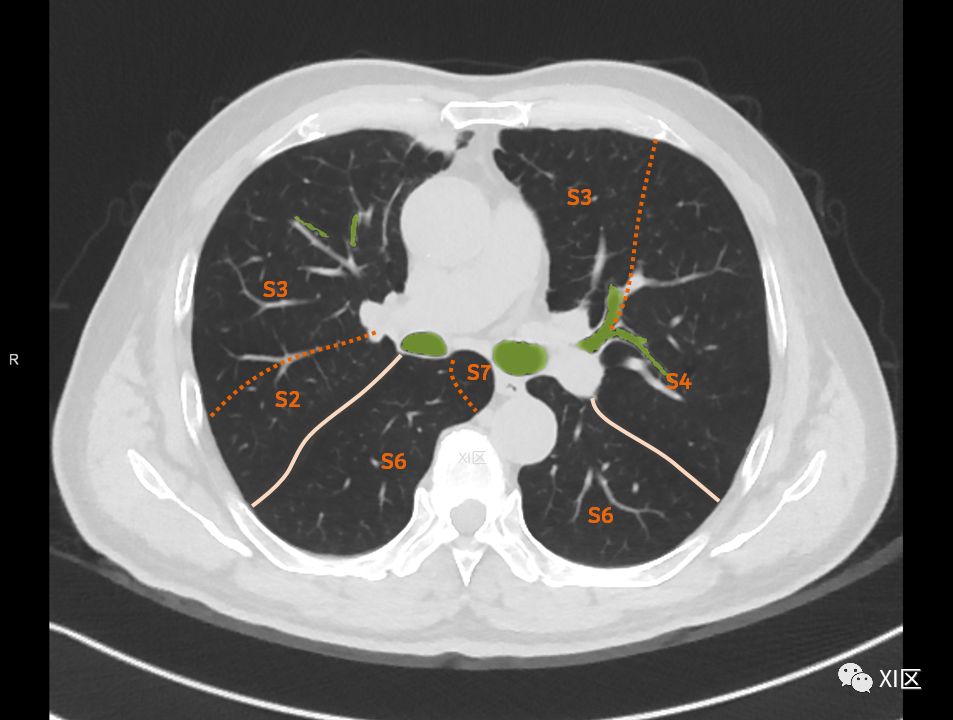

肺的断层分段示意图 医学百科网 | YxBaike.Com

在进行肺的分段时,可以上下观察浏览,沿着相应气管的走形可以更容易准确地进行分段。